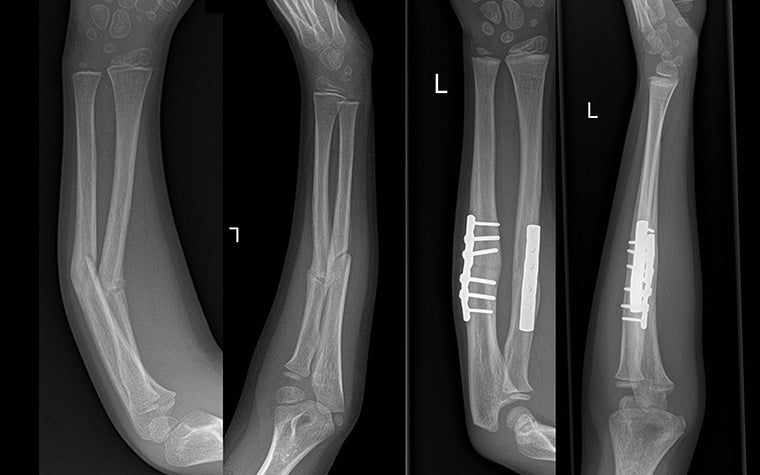

Dr. Verstreken has incorporated 3D technology into his practice for 14 or so years now, and many of his cases have benefited from 3D planning and printing. One that stands out is a seven-year-old child who had broken their arm in three places. Traditionally, just a cast would be enough to treat this type of break. However, for this patient, the cast mended the bones at an incorrect angle.

The process began by compiling CT scans of both arms into a 3D visualization. From there, Dr. Verstreken compared the mirrored 3D image of the healthy forearm with the abnormal forearm. And next came planning. He conducted a virtual surgery with the 3D visualizations, deciding where to lengthen and shorten bones, how exactly he should cut the bone, and where to insert the graft.

Based on this plan, the hospital's clinical engineer designed and printed the surgical guide. And by the time he stepped into the operating room, it felt to Dr. Verstreken as though it wasn't his first time completing this surgery. After placing the guide on the bone, it was smooth sailing.

"Once the guide is in the right place, it becomes fairly easy surgery because you know where to drill, you know where to cut," explains Dr. Verstreken. "And those [where to lengthen and shorten bones] are things that we would never be able to plan so precisely with standard two-dimensional X-ray."